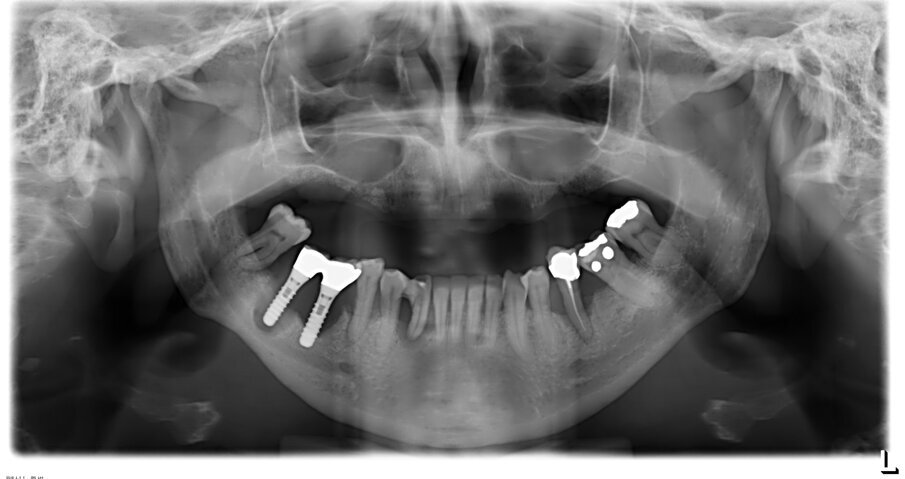

Nei casi di atrofie marcate, è fondamentale ricostruire l’osso mancante ma anche poter dare all’arcata una forma ideale. In questo caso clinico la paziente si presenta alla mia osservazione con una marcata atrofia del mascellare superiore (Fig. 1). La valutazione clinica è stata effettuata con esami radiografici di routine, OPM ed endorali, ma soprattutto con una Cone Beam TC. Da alcuni anni infatti, effettuo tutte le valutazioni diagnostiche in ambiente CAD con un software di chirurgia computer guidata che consente di valutare l’osso residuo in relazione al posizionamento tridimensionale dell’impianto protesicamente guidato.

L’approccio è quello di duplicare la protesi mobile utilizzata quotidianamente dalla paziente per renderla, attraverso punti di repere radiopachi, protesi radiologica. La paziente eseguirà la Cone Beam con la protesi radiologica e grazie alla presenza dei punti di repere radiopachi si potrà fare il matching tra i dati DICOM e la protesi della paziente (Figg. 2-4). Durante questa prima valutazione risulta evidente l’assenza di osso attorno agli impianti. La marcata perdita ossea è prevalentemente orizzontale e si estende in senso antero-posteriore su tutta l’arcata mascellare. Nella zona degli incisivi il posizionamento protesicamente guidato non è possibile a causa dell’assenza orizzontale dell’osso. Nelle zone posteriori inoltre si evidenziano i prolassi dei seni mascellari che riducono ulteriormente la disponibilità ossea. Di fronte a un quadro clinico così complesso si rende necessaria una scelta oculata della tecnica ricostruttiva adeguata.